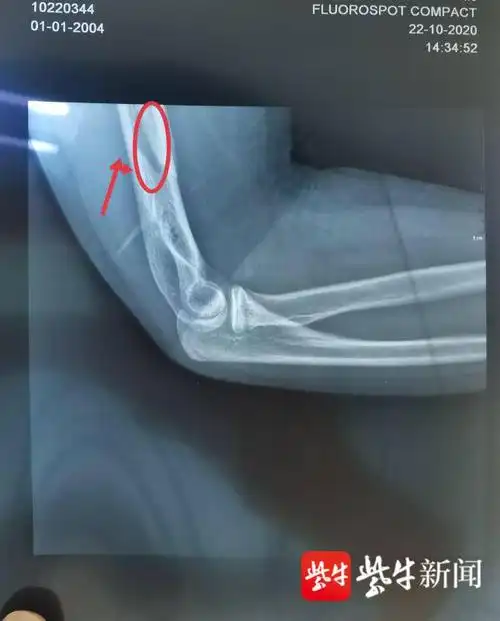

学生比力气掰手腕导致肱骨骨折